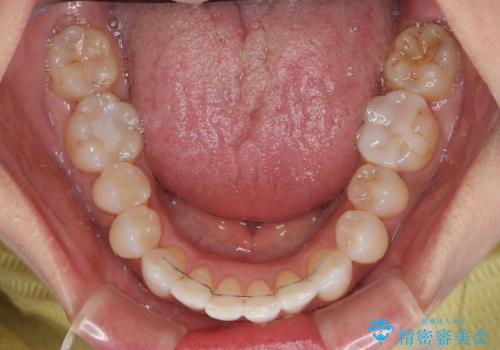

前歯のデコボコとむし歯治療の跡 インビザライン矯正とオールセラミッククラウン治療

デコボコの程度は中等度であったため、インビザライン・モデレートパッケージにて歯列を整えることとしました。

セラミッククラウンの装着されていた前歯と、大きな修復治療の跡がある反対側の歯は、矯正治療後に補綴治療を行うこととしました。

奥歯の欠損はインプラント、ブリッジ、入れ歯のどれにすれば良いかを決められず、仕事が非常にお忙しいこともあり、保留としたまま治療を終えることとなりました。

後戻りのリスクがあるため、なるべく早めに欠損補綴治療を開始する予定です。